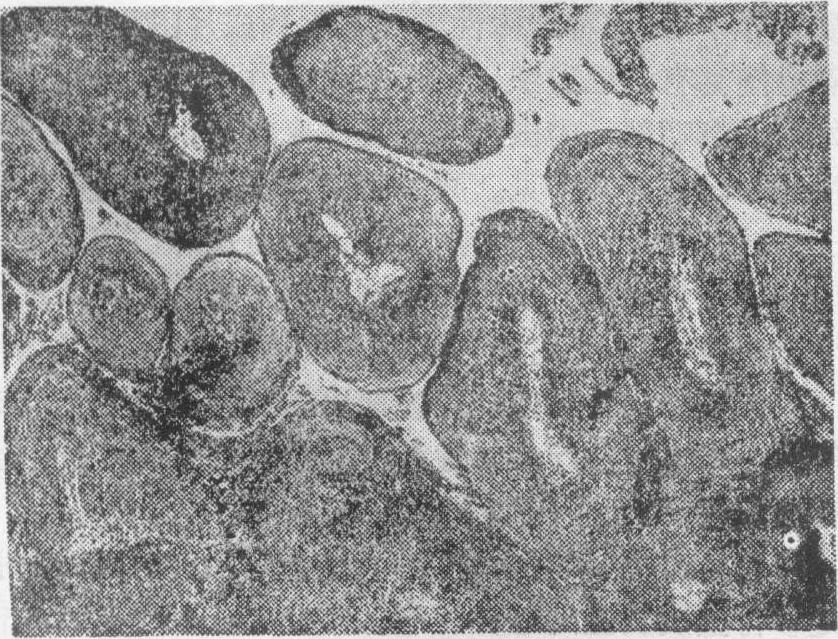

乳头状瘤为被覆上皮(包括鳞状上皮、移行上皮、柱状上皮和室管膜上皮)发生的良性肿瘤。肿块呈乳头状、菜花状或息肉状;大部分有蒂,少数基底广,无蒂。有时肿块的乳头状突起很纤细,似绒毛,称为绒毛状乳头状瘤。当其间质较丰富,胶原纤维较多时,肿块质地较硬(硬性乳头状瘤),间质少时则质软(软性乳头状瘤)。组织学上表现为分枝状富含血管的结缔组织索芯,表面覆以增生的上皮性肿瘤细胞,瘤细胞排列与正常的上皮组织排列相似,异型性不明显,核分裂象罕见,瘤细胞下的基底膜完整。乳头间质内伴有或不伴有炎性细胞浸润。乳头状瘤依其发生上皮的种类,可分为鳞状细胞乳头状瘤、基底细胞乳头状瘤、移行细胞乳头状瘤、柱状细胞乳头状瘤、室管膜乳头状瘤和脉络丛乳头状瘤等;依其生长方式,可有向表面生长形成的外生性乳头状瘤和向内生长的内生性乳头状瘤之分。外生性乳头状瘤远较内生性多见。

肿瘤的一种。由覆盖上皮或腺上皮发生的乳头状良性肿瘤。多见于马、牛、羊的头、颈、外阴、乳房皮肤和口腔、食管、膀胱黏膜。肿瘤表面呈菜花状或绒毛状,根部狭窄,常形成蒂与基底部正常组织相连。显微镜下,每个乳头以含有血管的分支状结缔组织间质为轴心,表面覆盖增生的上皮。